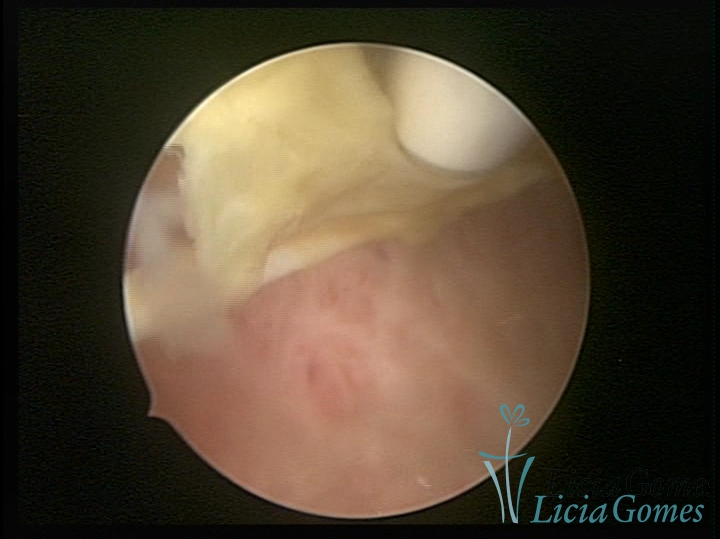

Cicatriz de cesárea com fio de sutura, não absorvido, como corpo estranho

×